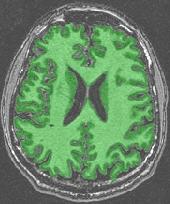

An illustration of the process at the level of a slice:

You can for instance visualize simultaneously the bias corrected image and the brain mask, relying on Anatomist linked cursor:

Another way consists of the two volume fusion. brainVISA's eye can do it for you. If you prefer manual work, select the two volumes, give a unicolor colormap with the ufusion extension to the mask, and choose the linear combination fusion mode: